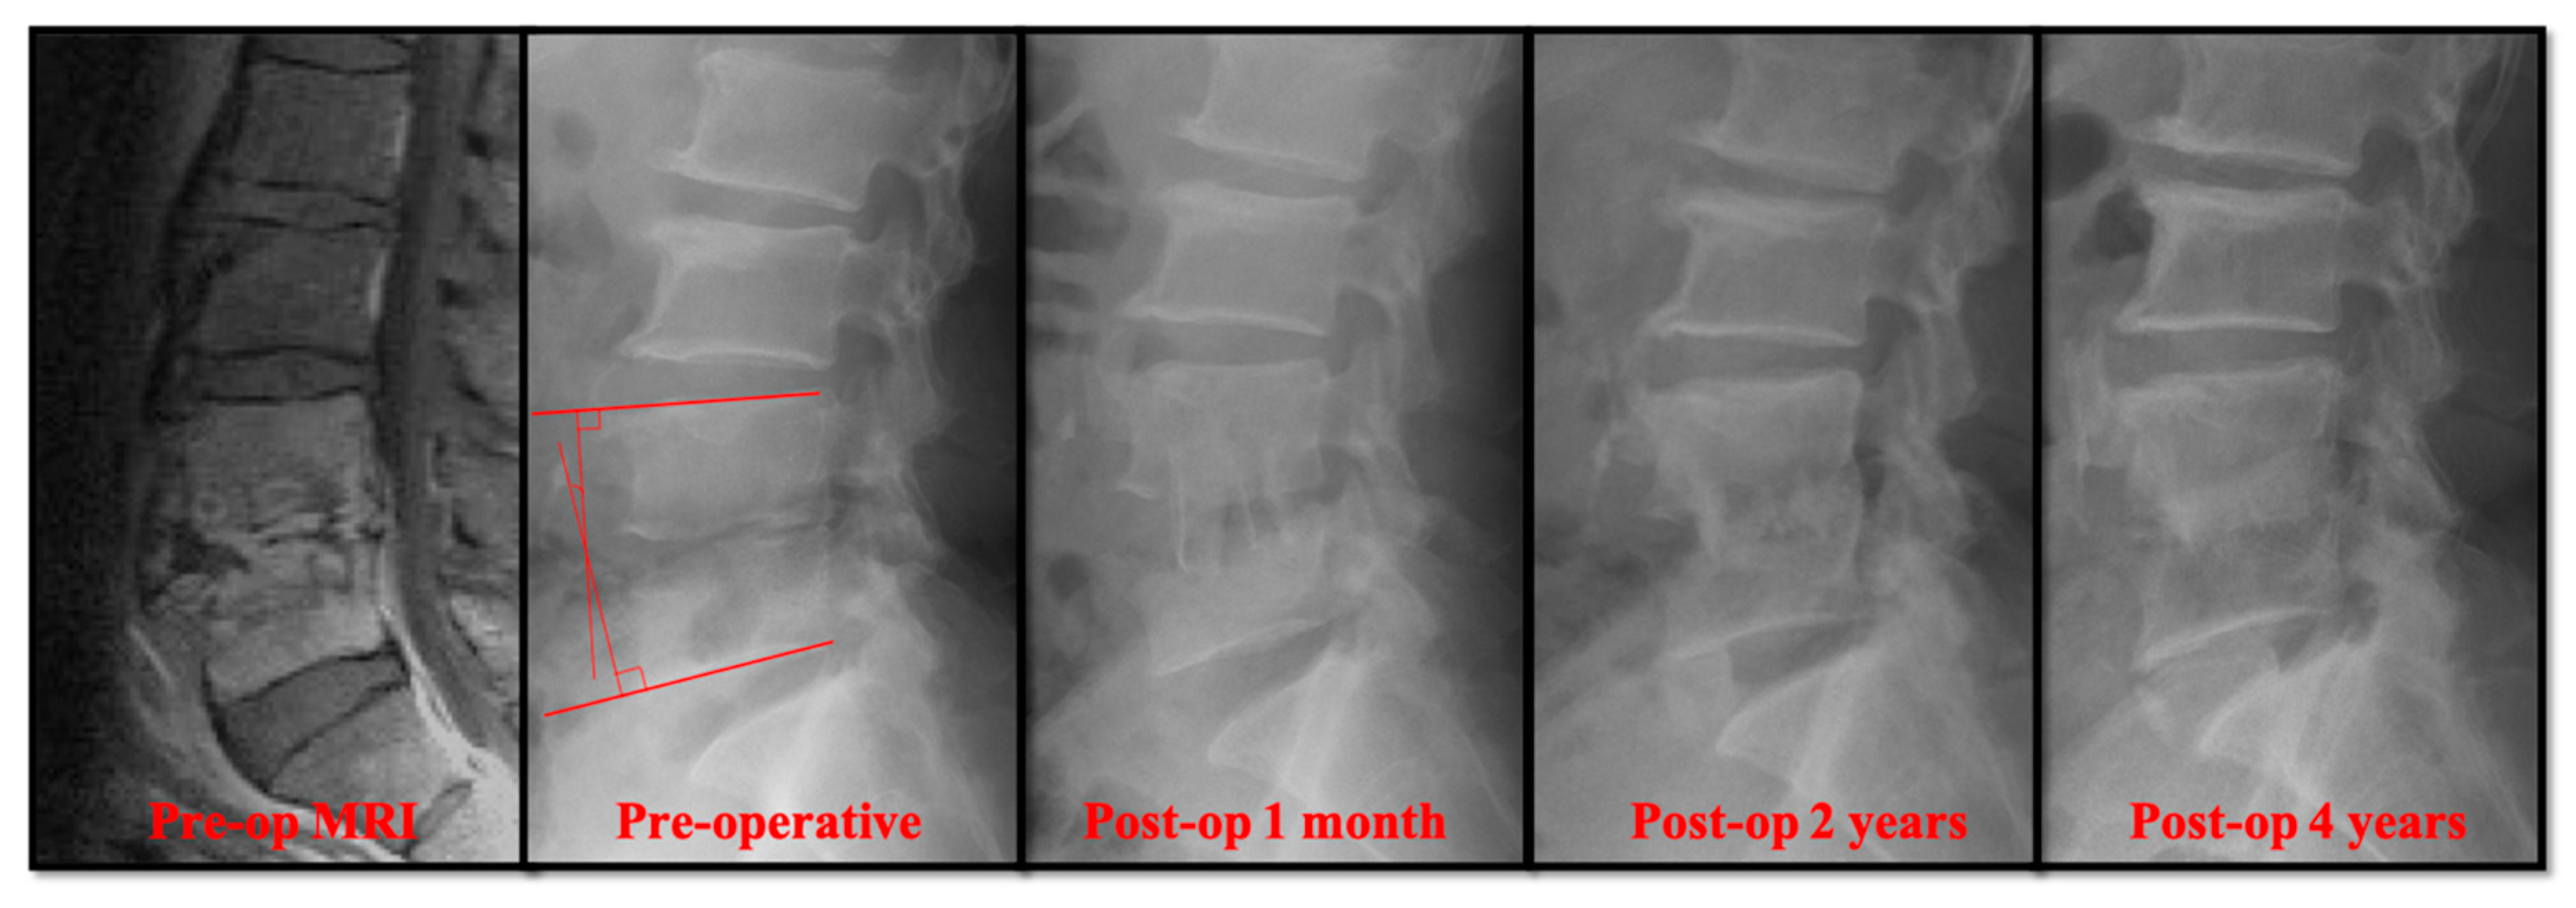

Radiographically, the primary correction gain after surgery was slightly higher in the open surgery group (Table 2). However, there was no significant difference in the change of sagittal profile, including primary correction gain (2.20° ± 2.91° versus 3.04° ± 3.65°), correction loss (2.41° ± 3.92° versus 3.68° ± 2.76°), and actual correction gain/loss (−0.21° ± 5.59° versus −0.64° ± 5.01°). In the follow-up radiographs, the successful bony fusions of the infected segments appeared in most of the anterior open surgery cases (Figure 1). A successful bone fusion was determined by continuously trabecular bony bridging between vertebrae and bone graft. There was no change in the sagittal angle of the targeted spinal segment between flexion-extension dynamic plain radiographic views because not every patient would consent to computerized tomography scans. Twenty-six out of 30 (86.7%) open surgery patients showed solid fusion at two years for the follow up. Nevertheless, 8 patients had obvious subsidence of the bone grafts due to damaged endplates in the early periods. Conversely, the destructive endplates of the infected segments became sclerotic, although decreased intervertebral disc height and local kyphosis were observed after successful treatment in the PEDD group (Figure 2). However, the motion of these infected spinal segments was still preserved after successful PEDD treatment. In the longer follow up, two patients showed spontaneous fusion in the PEDD group (Figure 2).

Figure 2. A 36-year-old man presented with severe pain in the lower back and leg. He was diagnosed with L3–L4 methicillin-resistant Staphylococcus aureus infection. The destructive endplate of the infected L3–L4 segment became sclerotic change although decreased intervertebral disc height and local kyphosis were observed after successful treatment in the PEDD group.